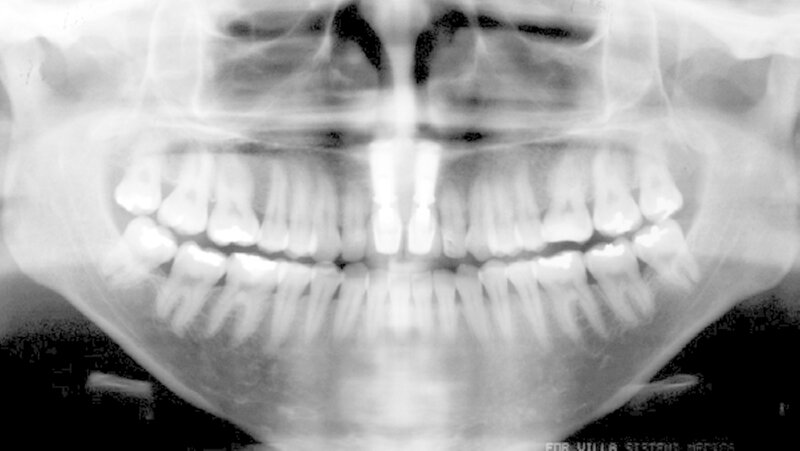

Die obere und untere Ausrichtung und Nivellierung der Bühne wurden mit bis zu 0,48 x 0,63 mm Edelstahldrähten fortgesetzt. Die präoperative seitliche Radiografie zeigte, dass die labiale Abwinklung der Implantate reduziert und die Positionen der unteren Schneidezähne abgeschwächt werden konnte. Vier Monate nach der Operation erhielten die Implantate Kronen in Übereinstimmung mit der Bogenmorphologie.

Die Dysgnathiechirurgie wurde mit Förderung des Oberkiefers durchgeführt, um ein angemessenes Gesichtsprofil und eine Okklusion herzustellen. Nach Abschluss der kieferorthopädischen Behandlung wurden erneut Fernröntgenbilder gemacht und die Drähte so gebogen, dass ein guter Okklusionskontakt entstand.